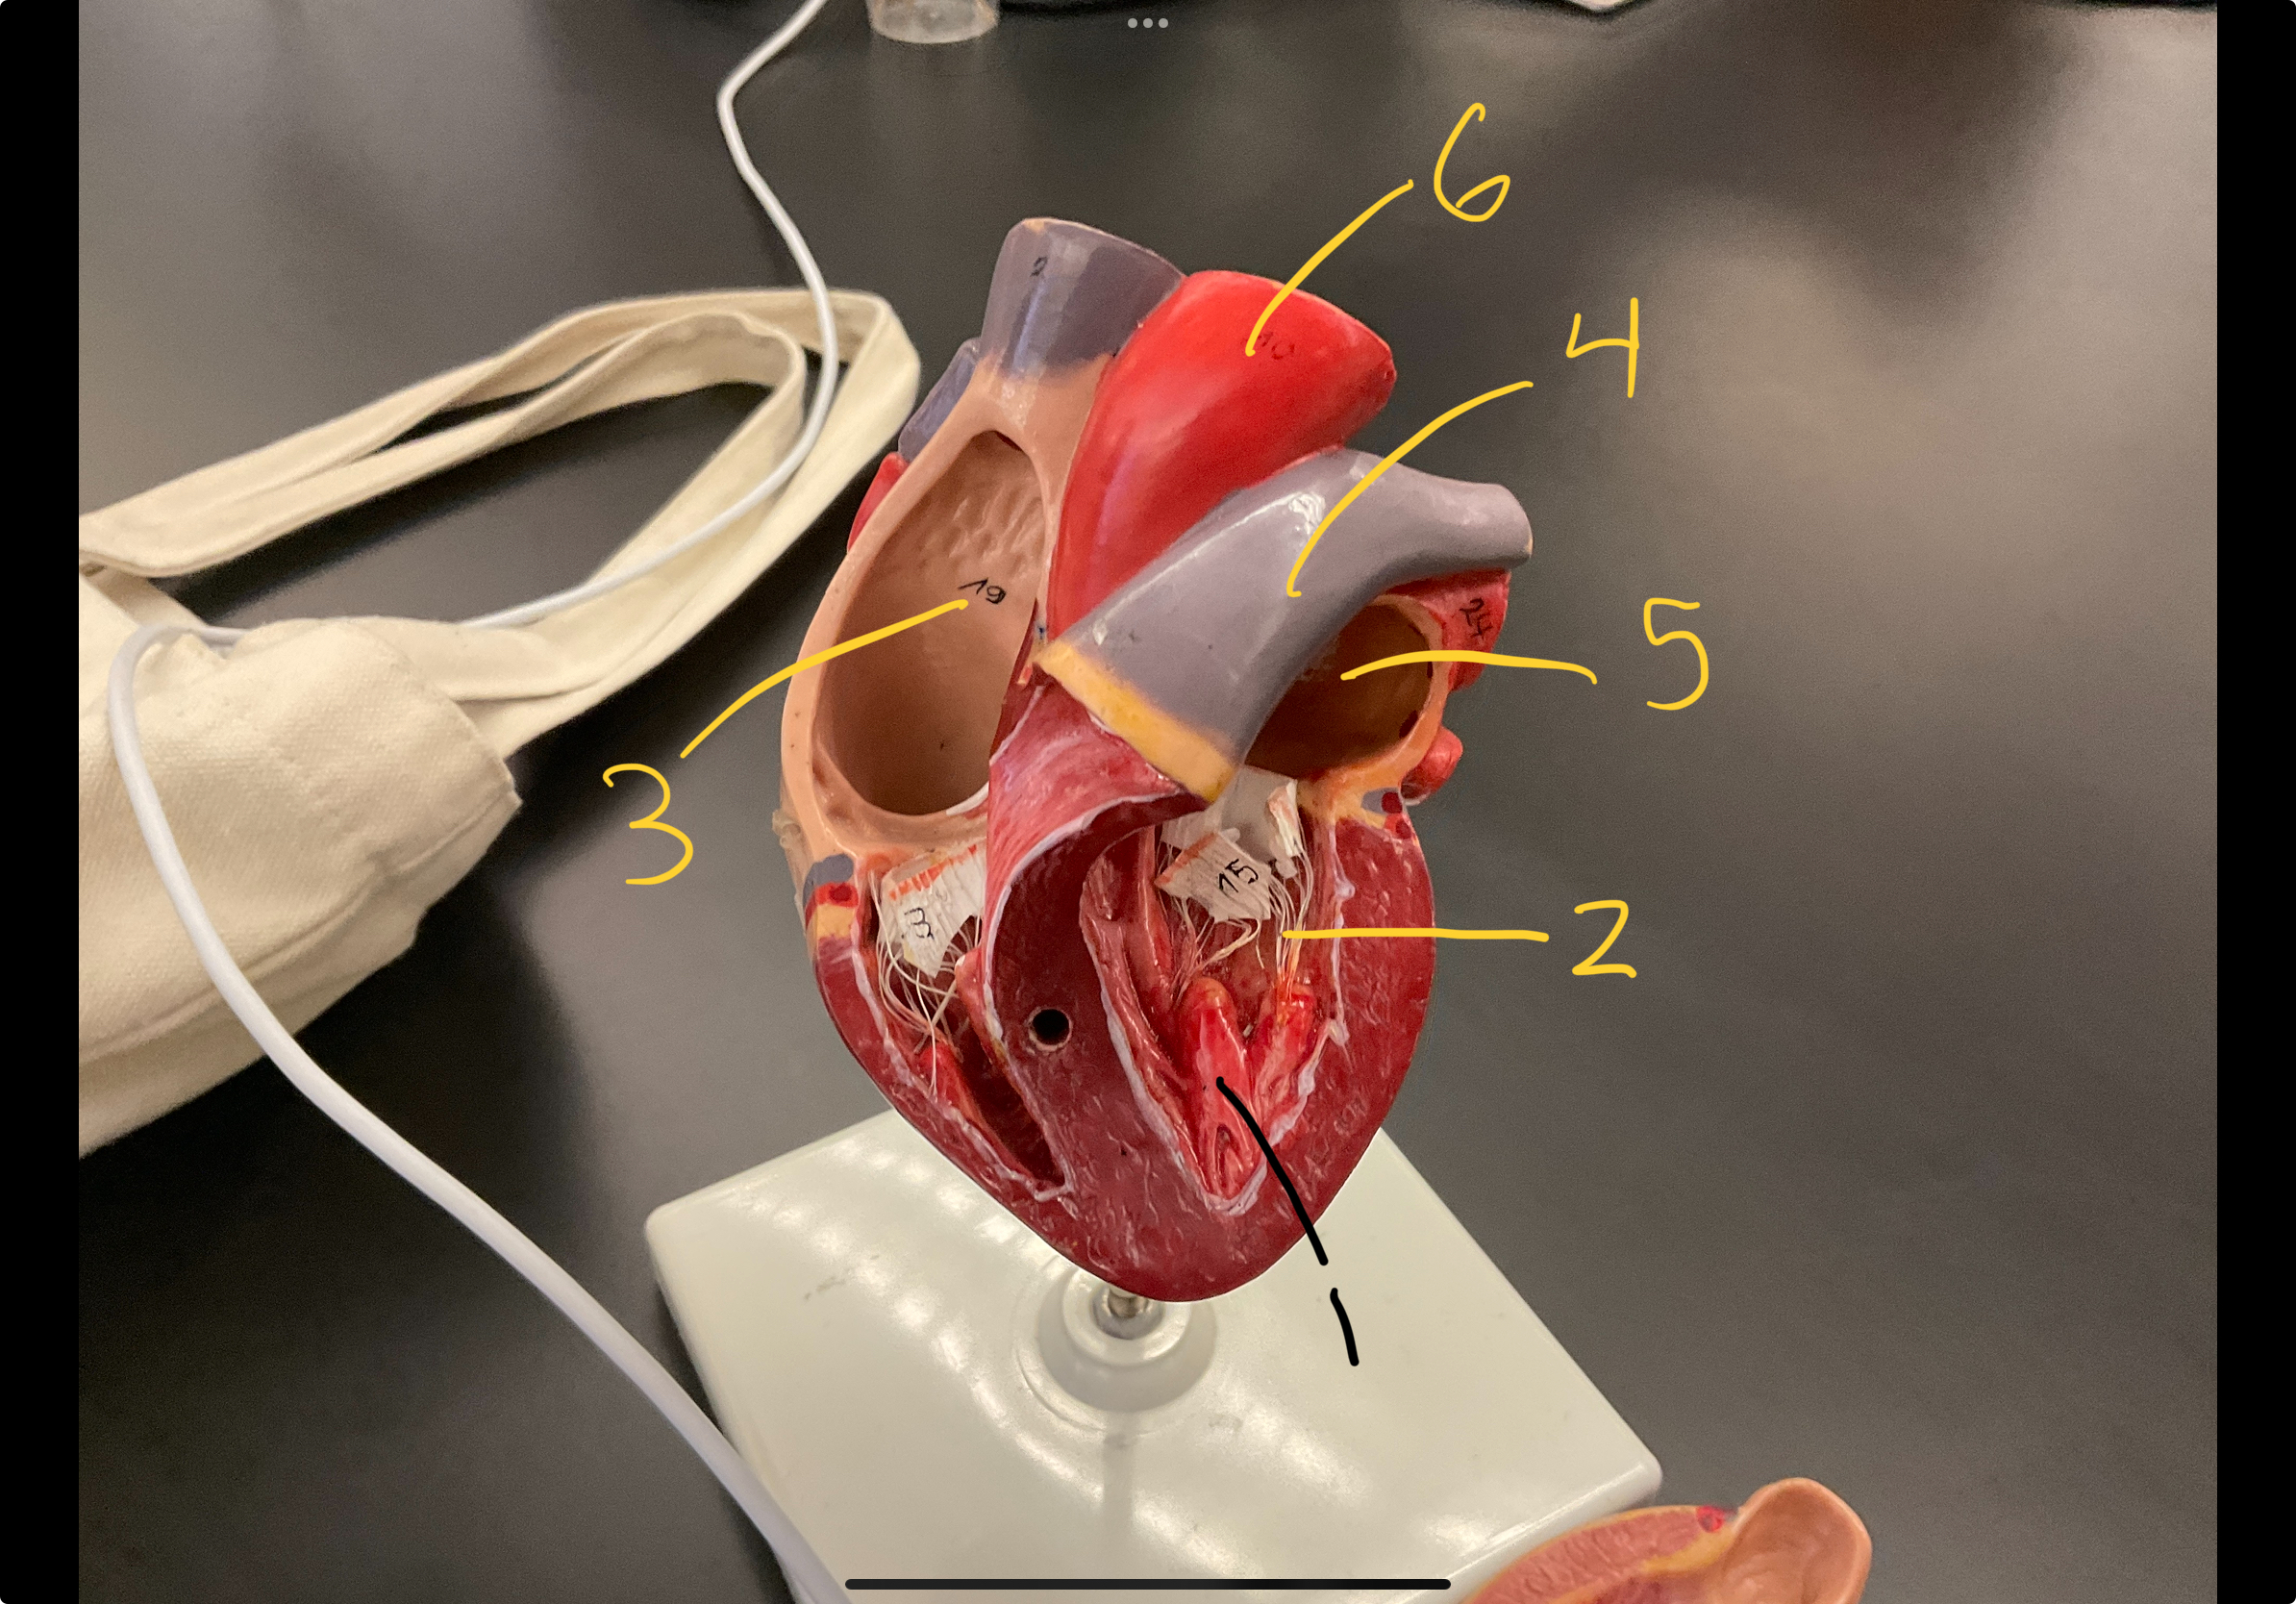

1

epicardium

2

3

endocardium

3

2

myocardium

4

1

coronary sinus

5

2

inferior vena cava

6

3

superior vena cava

7

1

right ventricle

8

2

left ventricle

9

3

bicuspid

10

4

tricuspid

11

5

interventricullar septum

12

6

left atrium

13

7

aorta

14

8

aortic trunk

15

9

pulmonary semi-lunar valve

18

1

papillary muscle

19

2

chordae tendineae